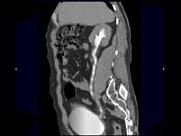

问题 男,47岁,腰痛、腰胀2月余伴低热、乏力,如影像资料所示,下列哪项说法正确 ( )

选项 A.右侧输尿管多发性狭窄,呈“串珠样”改变 B.右侧输尿管多发性生理性狭窄 C.右侧肾盂轻度积水 D.考虑为右输尿管占位病变 E.考虑为右输尿管结核

答案 ACE